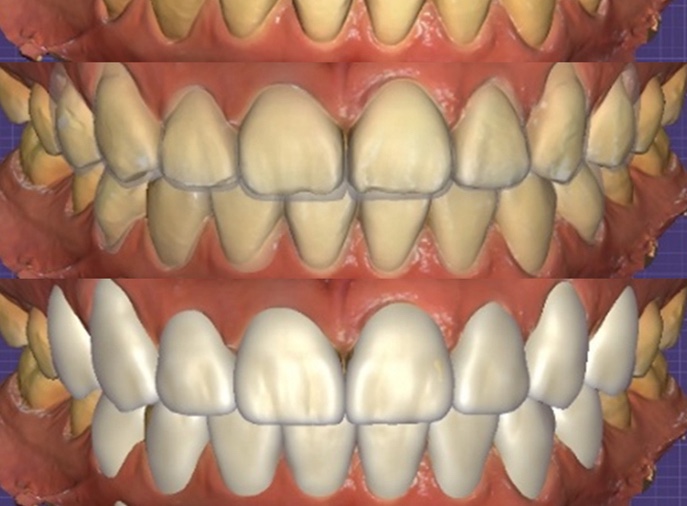

이에 따라 저희는

자연광에 가까운 투명도,

부담스럽지 않은 밝기,

입술 라인과 조화되는 앞니 길이,

발음이 편안한 절단면 형태를 기준으로

디자인 방향을 잡았습니다.

시뮬레이션 화면을 통해

예상 모습을 함께 확인해보니

“바로 이 느낌”이라며 치료를 진행하기로

결정하셨습니다.